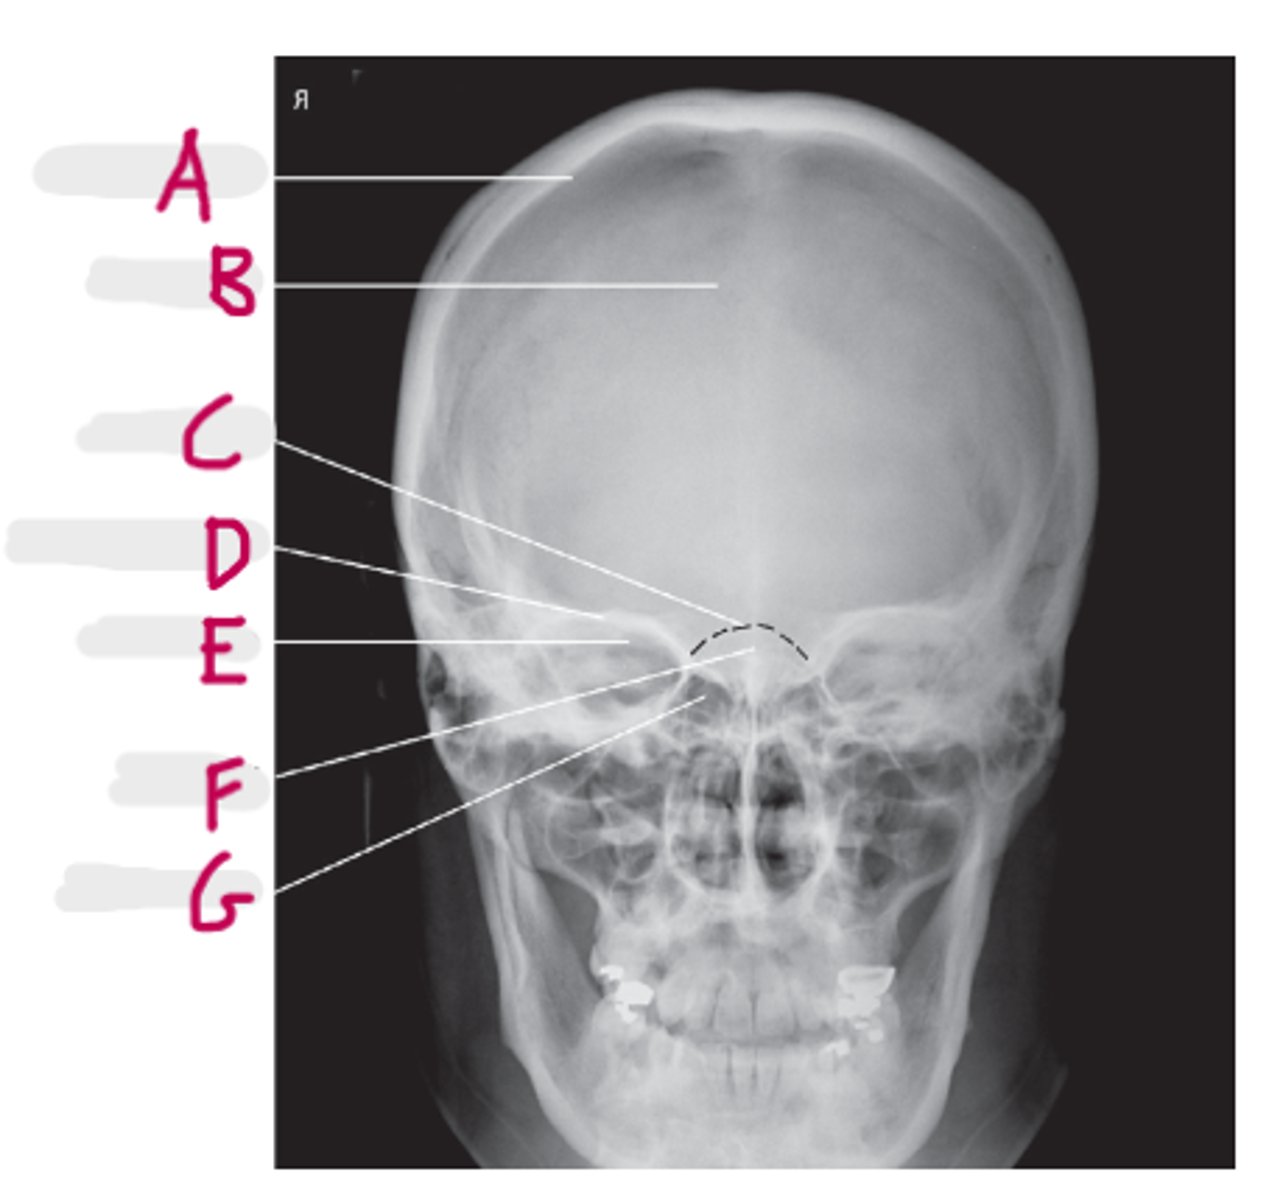

Frontal Sinuses

A

Ethmoid Sinuses

B

Maxillary Sinus

C

Petrous ridge

D

Mastoid air cells

E